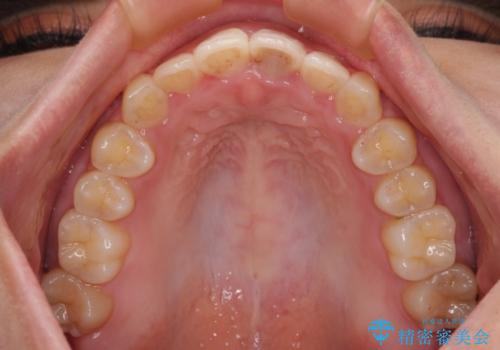

治療途中に上顎前歯が歯髄壊死を起こし、変色してしまいました。

痛みを感じたらすぐに連絡いただくよう伝えていましたが、忘れてしまっており、痛みと変色が発現したことで、すぐに連絡することを思い出されたとのことでした。

今後は、根管治療を行った後に、オールセラミッククラウンにて補綴治療を行う予定です。